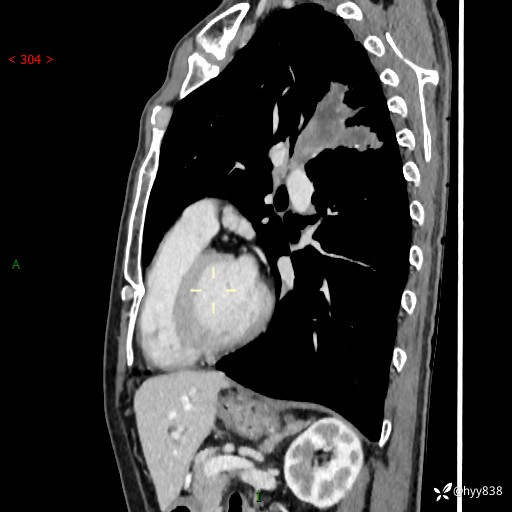

现病史:患者余4月前发现咳嗽咳痰伴痰中带血,无胸闷、胸痛、头晕、恶心、呕吐等不适,2天前因体检发现肺部结节遂于当地市第一人民医院行胸部CT薄层平扫+三维重建示:1.左肺上叶尖后段占位性病变考虑肿瘤性病变伴阻塞性肺炎,右肺上叶后段磨玻璃结节。2.肝内多发囊性灶、左肾结石。现患者为求进一步治疗,于我院门诊就诊,门诊以“肺结节”收入院。 自患病以来,精神、饮食、睡眠尚可,大小便正常,体力体重无明显减轻。

胸部CT增强扫描(外院平扫)